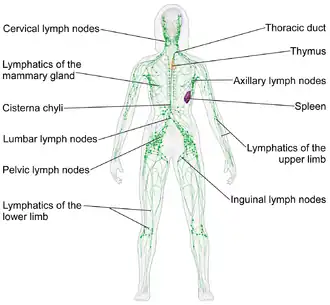

Location

Lymph nodes are present throughout the body, are more concentrated near and within the trunk, and are divided into groups.[5] There are about 450 lymph nodes in the adult.[5] Some lymph nodes can be felt when enlarged (and occasionally when not), such as the axillary lymph nodes under the arm, the cervical lymph nodes of the head and neck and the inguinal lymph nodes near the groin crease. Most lymph nodes lie within the trunk adjacent to other major structures in the body - such as the paraaortic lymph nodes and the tracheobronchial lymph nodes. The lymphatic drainage patterns are different from person to person and even asymmetrical on each side of the same body.[6][7]

There are no lymph nodes in the central nervous system, which is separated from the body by the blood–brain barrier. Lymph from the meningeal lymphatic vessels in the CNS drains to the deep cervical lymph nodes.[8] However, the CNS does innervate lymph node by sympathetic nerves. These regulate lymphocyte proliferation and migration, antibody secretion, blood perfusion, and inflammatory cytokine production.[9]